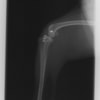

術前左後肢側面像

術後左後肢側面像

術前のTPAは左後肢33.1°右後肢26.8°でしたがTPLO実施により左後肢5.5°右後肢12°に矯正されました。